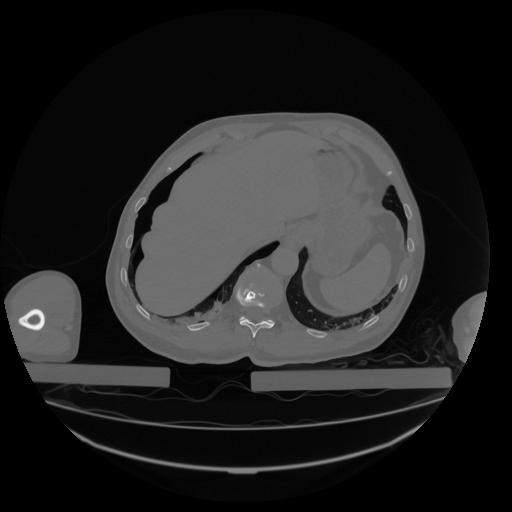

34 CUERPO,CE,Vol,1.0,CUERPO,,